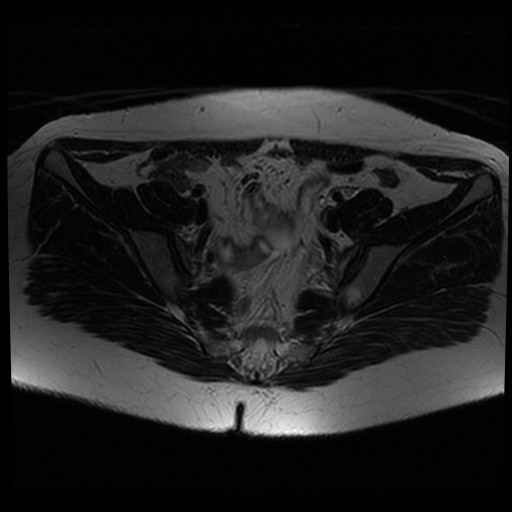

bekken